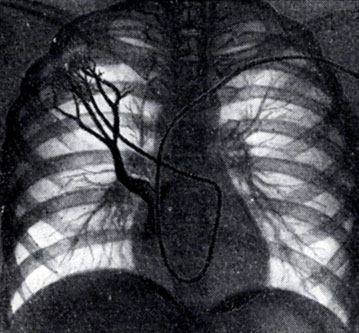

Ангіопульмонографія

Ангіопульмонографія - проводиться з метою діагностики тромбоемболії легеневої артерії, звуження стовбура легеневої артерії та ін.При загальній ангіопульмонографіі контрастну речовину вводять в стовбур легеневої артерії, при цьому заповнюються всі судини малого кола кровообігу. При селективної контраст вводиться лише в одну з гілок легеневої артерії і оцінюється стан кровотоку тільки однієї легені або його частки.